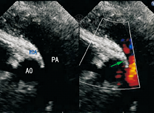

11例病例中超声心动图确诊10例,漏诊1例。超声诊断为左冠状动脉起源于右冠状窦并壁内走行4例(图1),右冠状动脉起源于左冠状窦6例(壁内走行2例,大动脉间走行4例)(图2)。超声心动图可清晰显示病变冠状动脉是否壁内走行等情况。1例合并完全性肺静脉异位引流者超声心动图检查未发现冠状动脉起源异常。

注:AO:主动脉;PA:肺动脉;RCA:右冠状动脉 AO:aorta;PA:pulmonary artery;RCA:right coronary artery

11例病例行心脏多层螺旋CT检查,5例为左冠状动脉起源于右冠状窦(图1);6例为右冠状动脉起源于左冠状窦。